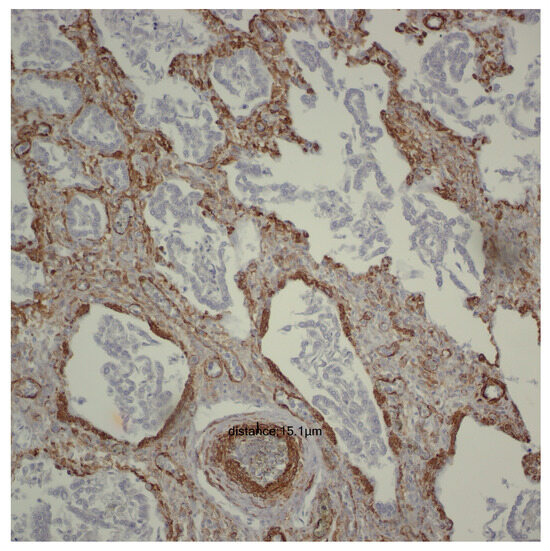

For the evaluation of the media layer of the vascular walls, a vertical line was drawn between the highest point and the lowest point, recording the values obtained for each individual case. To prevent inaccuracies in measuring the arteriolar media, tangentially captured vascular structures were deliberately avoided, with measurements taken exclusively at the level of transversely captured vascular structures (Figure 1).

Figure 1.

Smooth Muscle Actin (SMA) immunoreactivity at 200× magnification, illustrating the thickness of the vascular media.

After evaluating pulmonary microvascularization, we proceeded to examine larger vascular structures of the arteriolar type and assess the thickness of the arteriolar media by analyzing the SMA immunohistochemical marker (please refer to the evaluation protocol). We aimed to investigate whether the thickness of the arteriolar media was affected by the number of days of life and oxygen treatment, and we noted a positive correlation between them. As life expectancy rises, there is a tendency for an increase in the thickness of the arteriolar media (r = 0.22; p = 0.008) (Figure 8).